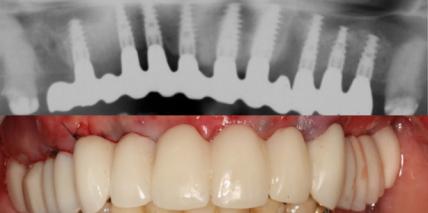

Der ältere Mensch – die navigierte Chirurgie

Durch die Zunahme der Lebenserwartung unterliegt die Altersverteilung der Bevölkerungsstruktur einem deutlichen demografischen Wandel. Für die zahnärztliche Behandlung bedeutet dies einen Anstieg des älteren Patientenklientels, auch im Bereich der Implantologie.